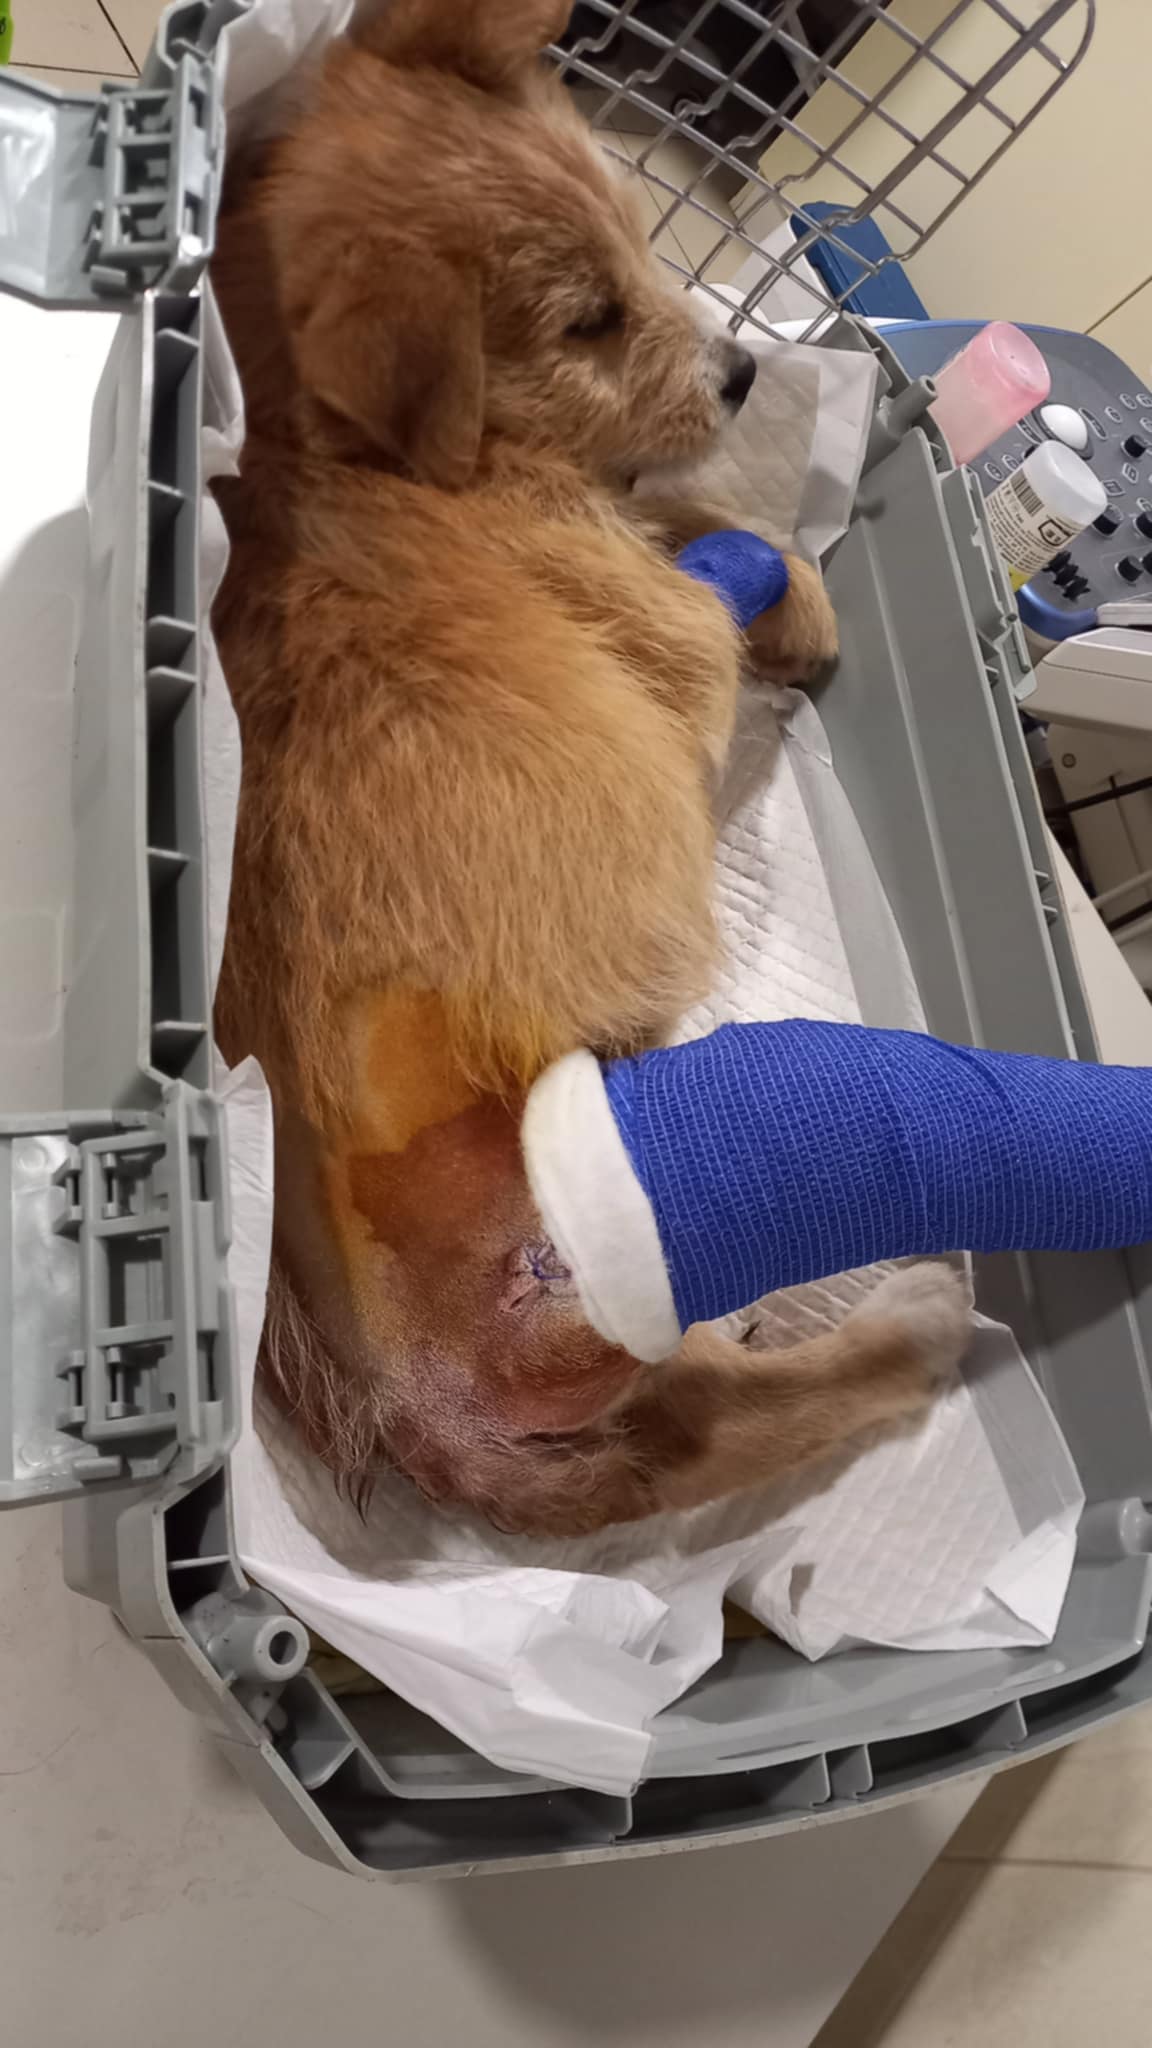

Nachdem die kleine Stella nach mehr als einer Woche die Klinik verlassen durfte, Mussten erneut einige unserer Neuzugänge dringende Not-OP´s und stationäre Aufnahme +ber sich ergehen lassen. So auch der kleine Sidney, den wir schwer verletzt mit gebrochenem Hinterbeinchen auf der Strasse in Nordungarn fanden. Sofortige Untersuchungen, Rüntgenaufnahmen und unverz+gliche Notoperation war erforderlich. Die Operation hat der kleine Mann gut überstanden. Nun benütigt er weitere Medikamente und Vitaminprodukte, damit er einen guten Heilungsprozess durchlaufen kann. Ebenso benütigt er 6 Wochen Zwingerruhe und Physiotherapie.